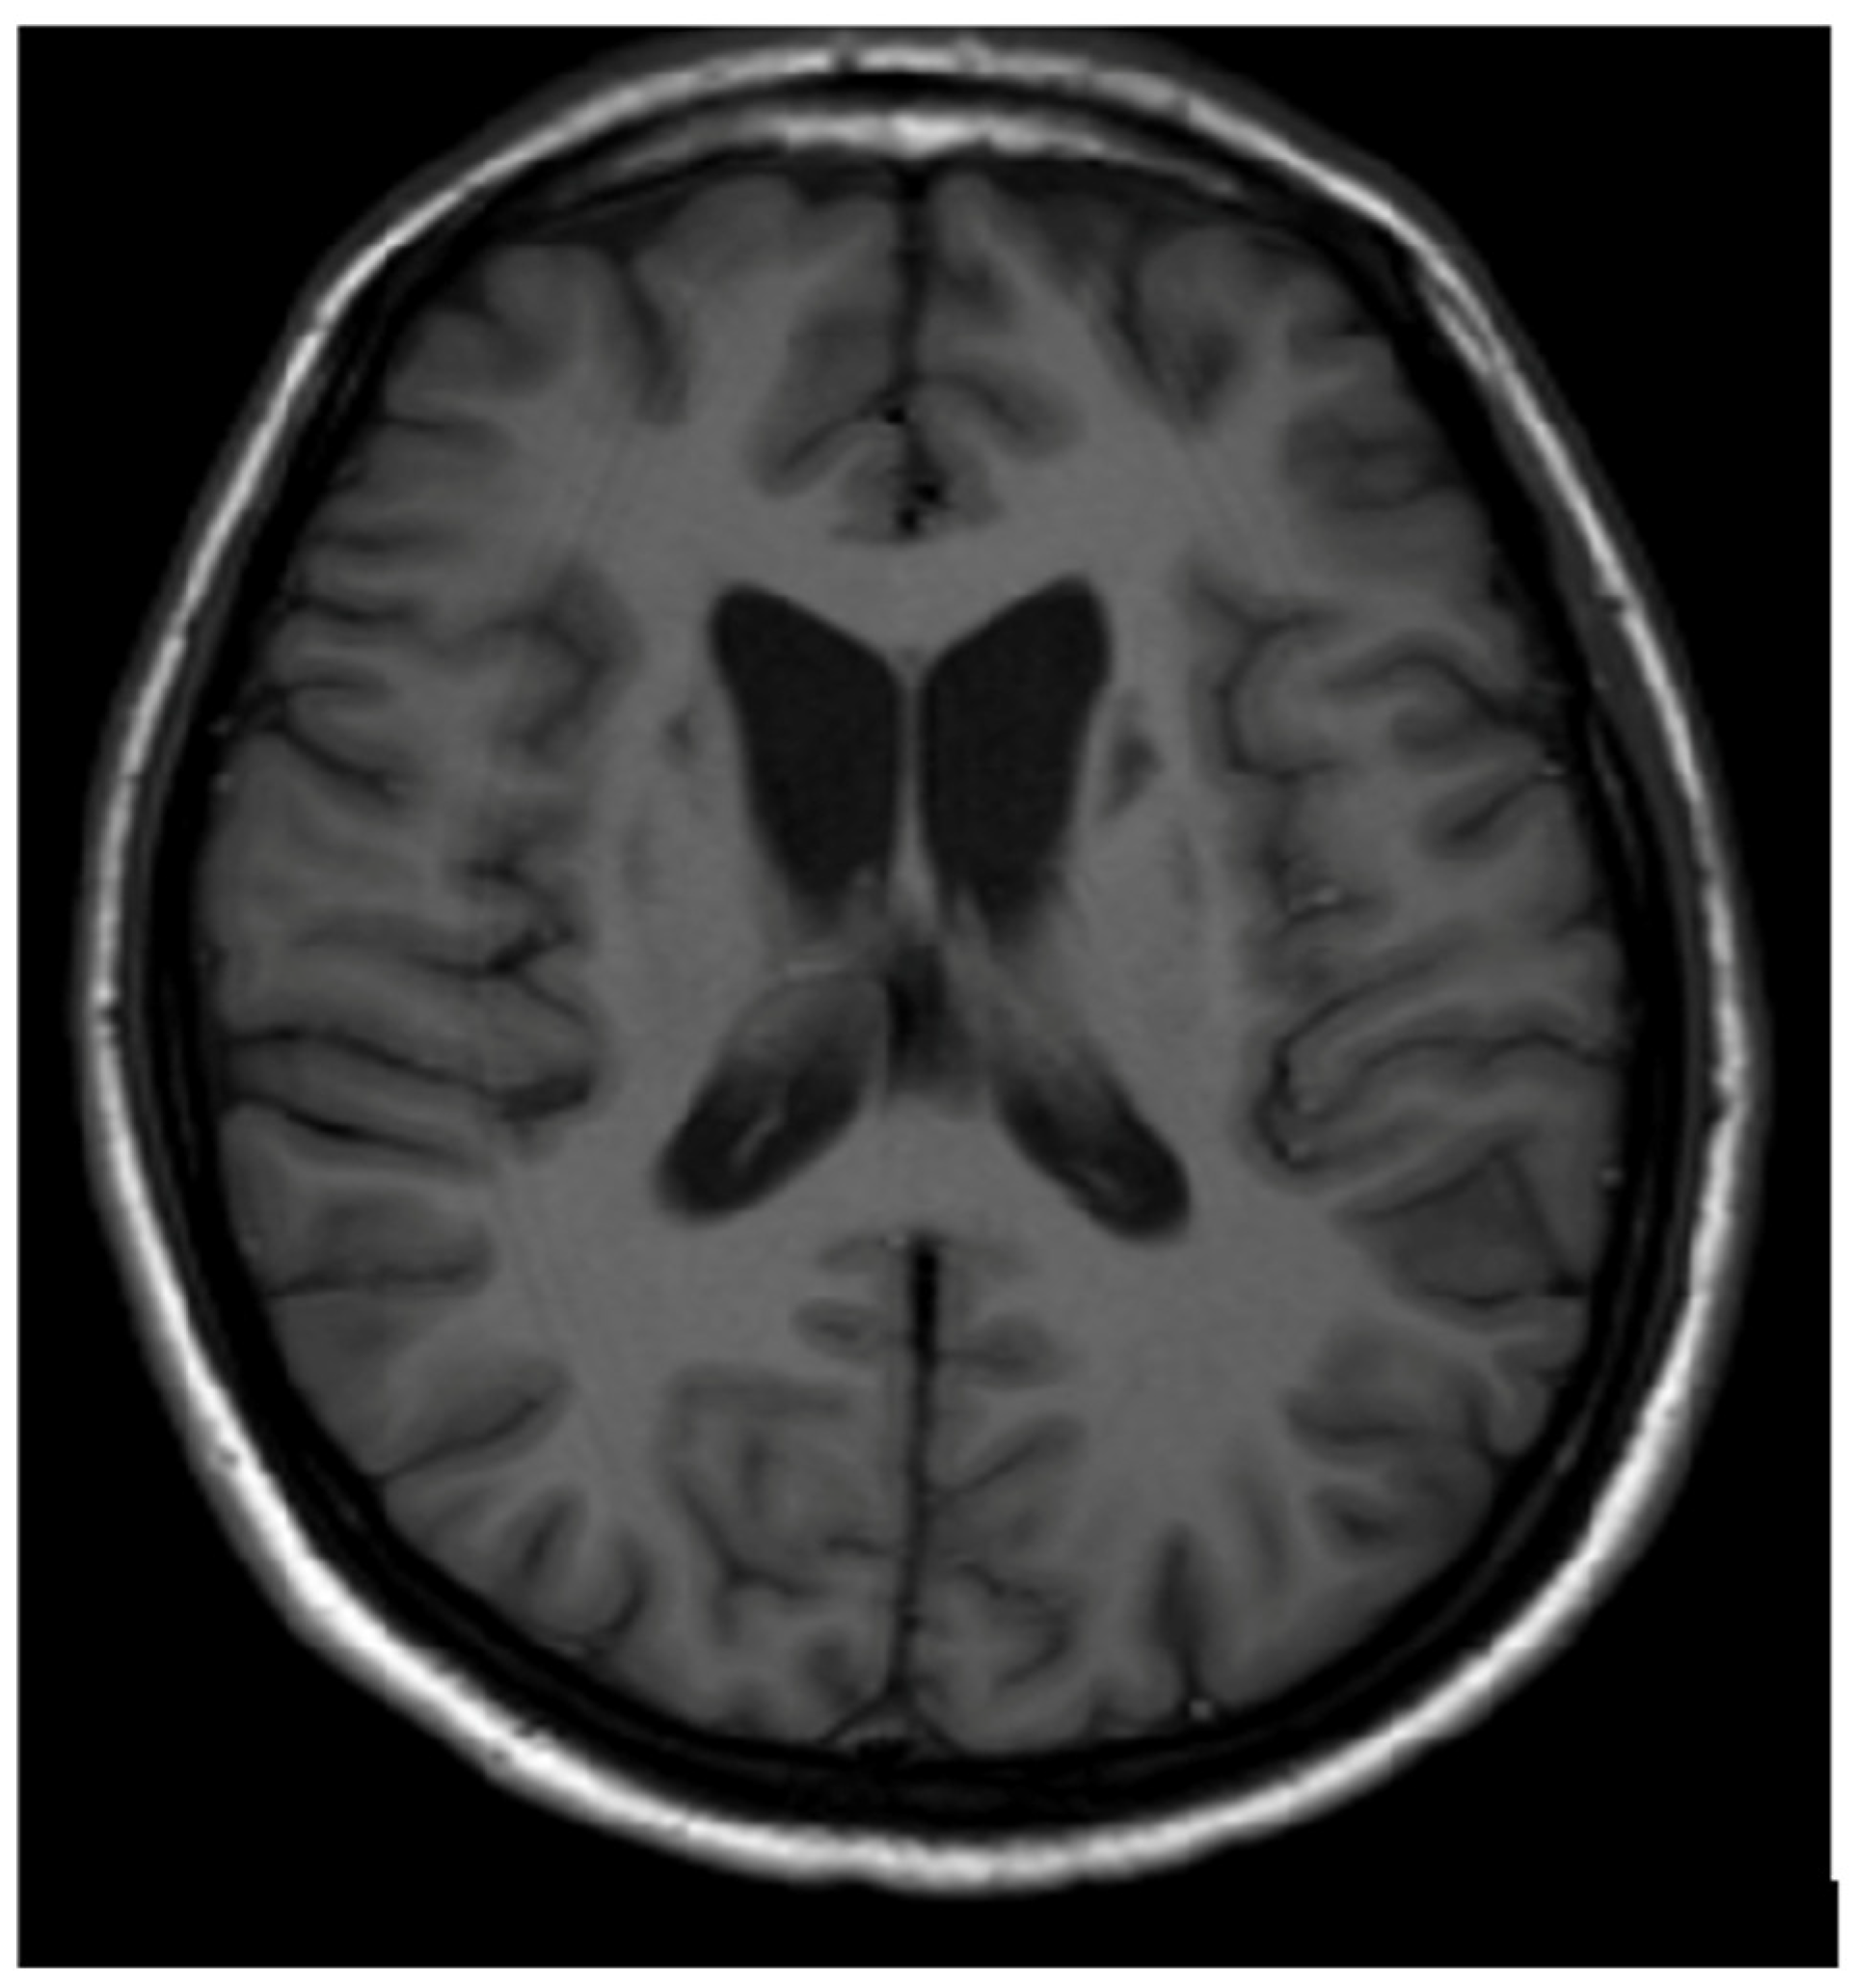

In cases of advanced disease (long-term and untreated), brain MRI changes may appear as hypointense areas on T1-weighted images (necrosis or atrophic changes) [12,13,14,15,16,17,18,19,20,21] (Figure 3). It should be noted that several metabolic, genetic, neoplastic, and inflammatory disorders can involve the basal ganglia symmetrically. Occasionally, these disorders also affect other brain structures, sometimes unilaterally. Brain MRI plays a supportive role in diagnosis and aids in differential diagnosis; however, without clinical symptoms and additional clinical, metabolic, genetic, etc., examinations, brain MRI alone cannot form the basis for disease diagnosis [1,2,3].

Hypointense changes localized in both putamen in T1-weighted images (own materials of the neurology department).

In some cases, white matter (up to 20% of WD patients) and the corpus callosum may also be affected. As WD is primarily a hepatic disorder, severe liver pathology (liver failure, hepatic encephalopathy (HE)) can result in symmetrical hyperintense changes in the globus pallidus and substantia nigra on T1-weighted images, likely due to manganese intoxication similar to those observed in acquired hepatocerebral degeneration (AHD) [20] (Figure 4). However, these changes are not typical of WD but are more characteristic of AHD or HE.

Hyperintense changes localized in both globii pallidi in T1-weighted images (probably due to manganese accumulation) (own materials of the neurology department).